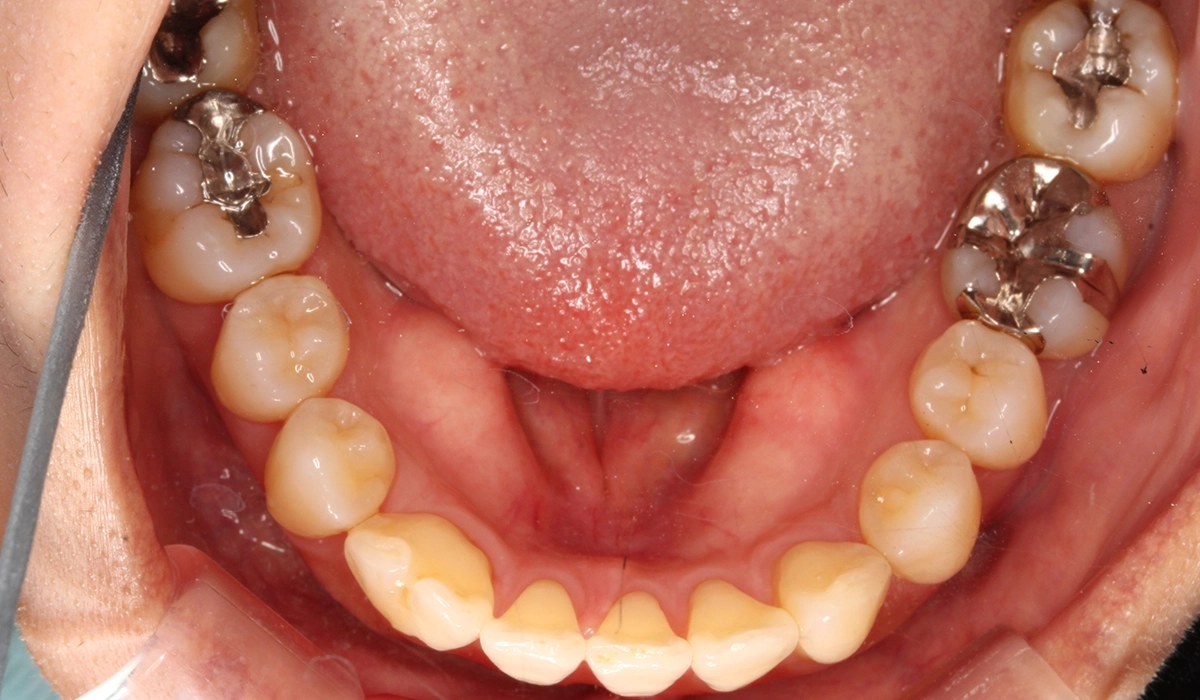

術前:下顎

術後:下顎